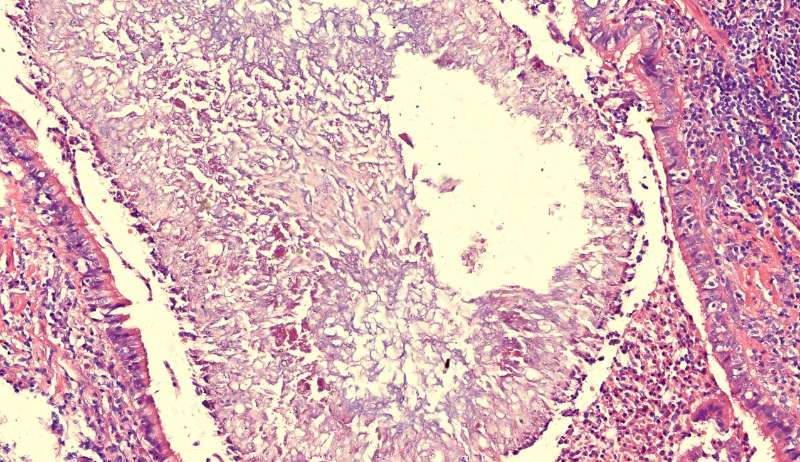

最后发一例化脓性炎症

中性粒细胞很多,此处组织结构破坏

左侧液化,脓肿壁较规则平滑

周围的炎症机化区

破坏力在这里逐渐减弱

逐渐从中性粒细胞转为淋巴细胞为主

周边区:

肺泡内有渗出,逐渐吸收 机化是不是纤维细胞增多看的?王:是的